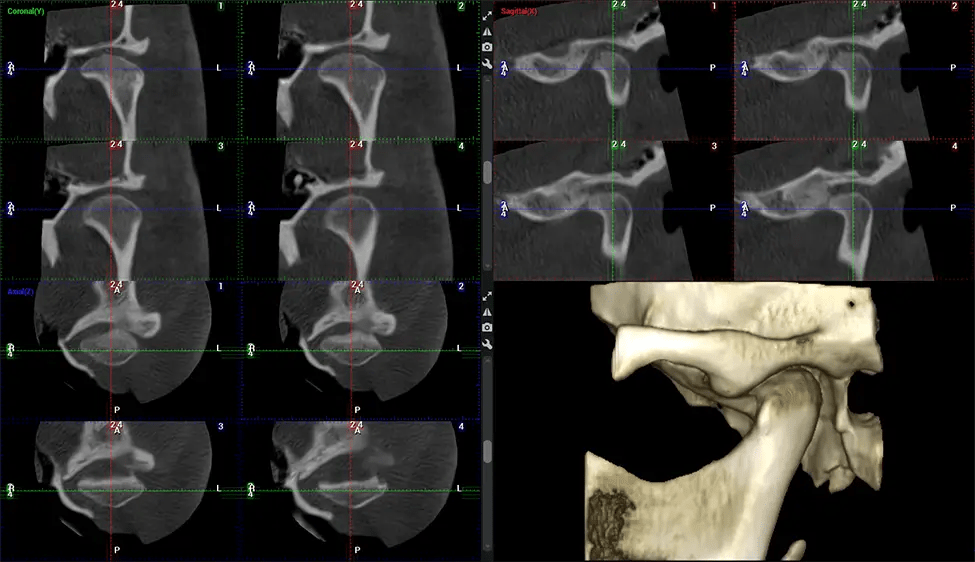

Upper Cervical Chiropractor Diagnosing structural problems in the C1-C2 vertebrae, assessing misalignment and instability, and evaluating chronic pain. Enables precise, weight-bearing views of the upper cervical spine, helping to identify abnormalities that inform targeted, non-invasive therapies.